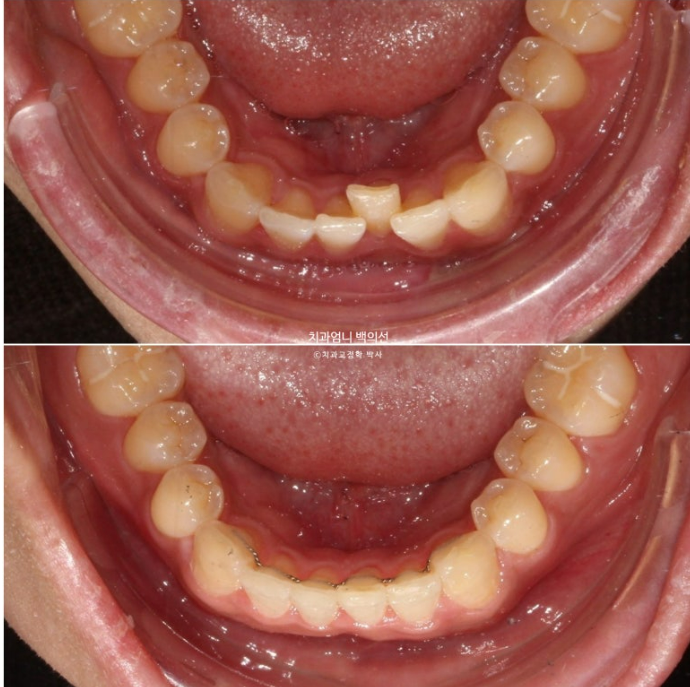

아래 앞니 중 안으로 쏙 들어가 있던 치아는 교정치료 전 후 위생 상태의 확연한 차이가 납니다.

치아가 삐뚠 부분에는 치태와 치석이 쉽게 쌓이는 데다가 일반 양치질로는 접근이 어려워 깨끗하게 닦이기 쉽지 않습니다.

교정 후 배열이 가지런해지니 유독 청소가 안되던 부위가 평소하는 양치질 만으로도 말끔해졌습니다.

25.02~25.06